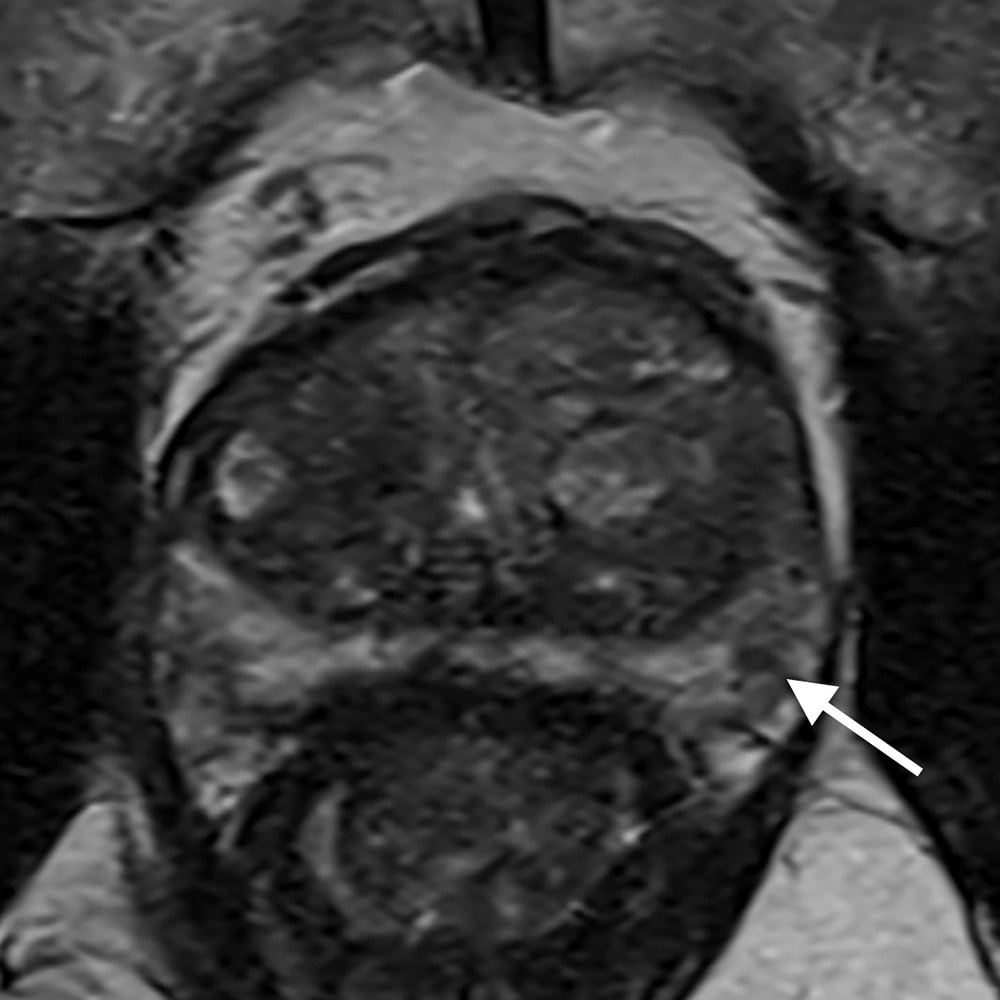

PSA高値(12.4)精査のため施行された1か月前のMRIは、直腸ガス多く、拡散強調画像で一部高信号疑うものの確証が得られなかった。そこで造影検査で再検したところ、微小なPI-RADS4病変が確認された。対象が小さいため、標的生検もふくめて見送り、経過観察している。

当該疾患の診断における造影MRIの役割

PI-RADS (prostate imaging reporting and data system)は、前立腺MRI診断の標準化として泌尿器科医にも広く知られ、前立腺癌診療に欠かせない一部となっている。PI-RADSスコアリングでは、T2強調像と拡散強調像の評価が重視され、造影は補助的な位置づけとなっている。T2強調像と拡散強調像のみを評価するbiparametric MRI (bp-mRI)の診断能が、造影を含めたmultiparametric MRI (mp-MRI)に劣らない、という報告が増え、安易にbi-MRIが多用されるきらいがある。

しかしbp-MRIは拡散強調像に負うところが大きく、拡散強調像は直腸ガスや体動、さらに撮像条件の影響で、安定した高画質を得ることが難しい。これに対し造影ダイナミック撮像は拡散強調像よりアーティファクトの影響を受けにくく、補助的、というよりは実臨床では診断の確診度を高め、フェイルセーフとしての役割が大きい。ガイドライン上も、bp-MRIで評価可能は、3テスラMRIをエキスパートが読影し、標的生検で確認できる施設でのみ、弱く推奨できるとしている。